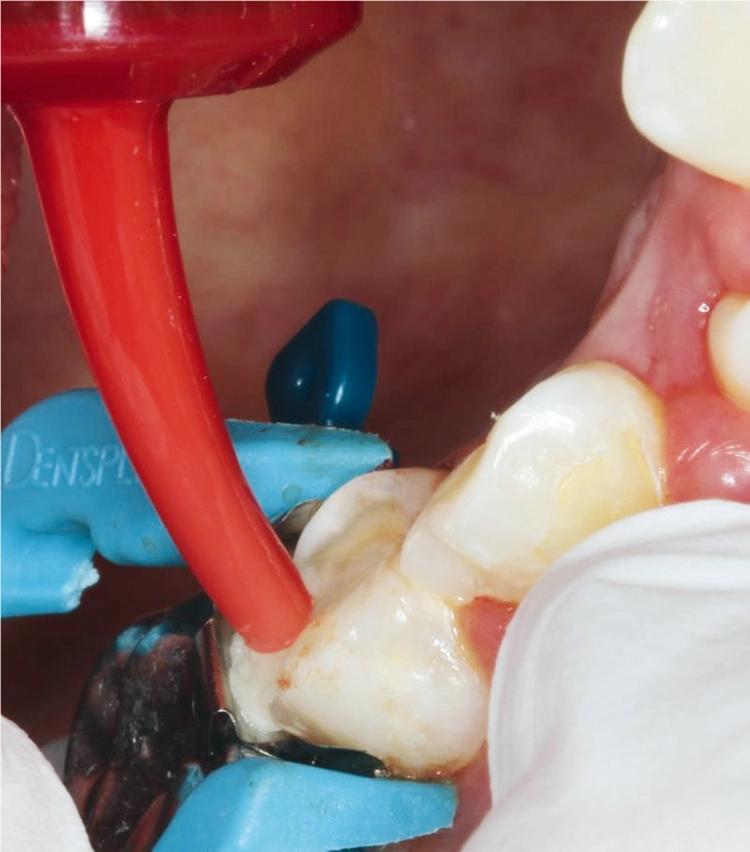

Möhn, KrämerHierzu wurde das Kapselpräparat per Hand auf einer stabilen Unterlage aktiviert und für 10 Sek. in einem Kapselmischer vermischt. Die Applikation des selbstadhäsiven Materials in die Kavität erfolgte in einem Schritt (Abb. 5).

Möhn, KrämerDank der modifizierten Polysäuren des verwendeten Komposithybrids konnte auf eine adhäsive Vorbehandlung des Zahnes verzichtet werden. Anschließend wurden die Überschüsse mittels Kugelstopfer entfernt (Abb. 6) und jede Fläche für 20 Sek. polymerisiert (SmartLite® Pro).

Möhn, KrämerDie Oberfläche kann dadurch direkt nach der Lichthärtung ausgearbeitet werden, während das Material noch in der Tiefe chemisch vollständig aushärtet. Das Abschlussbild zeigt die fertige Restauration nach Ausarbeitung und Politur (Abb. 7).